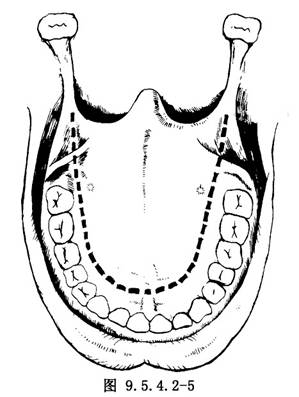

(1)切口:最常採用硬齶U形切口。自一側第3磨牙後端平面開始,切口直達骨膜下,繞向齶大孔內側,再向前大致與牙列平行向前延伸至切牙後1cm處,再彎向對側形成U形切口(圖9.5.4.2-4)。爲了擴大術野,U形切口的一端可移至齶大孔外側,將齶大動脈切斷結紮,也可將切口後端兩側向後外延向舌齶弓,但切不可結紮兩側齶大動脈,以免黏骨膜瓣壞死。在翼突溝外將齶帆張肌切斷,軟齶即可拉向後方(圖9.5.4.2-5)。如腫瘤向翼齶窩擴展,可將切口後端繞過腫瘤一側的上頜粗隆加做頰齦切口(圖9.5.4.2-6)。